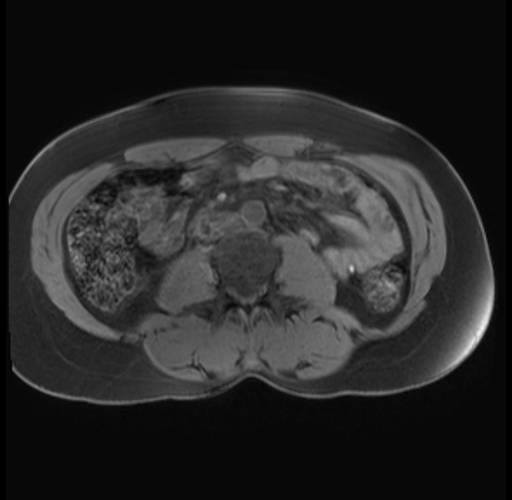

Imaging Analysis

Look through the patient's CT scan to identify any areas of concern for the necessary procedure.

Based on your CT findings, which issue(s) are present and would give reason for "planned slowing down moment(s)" in this case?